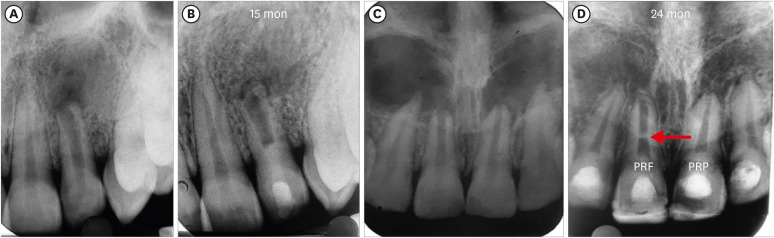

3. AFD, RWT, and RL

Figures 7, 8, 9 shows the measurement of AFD, RWT, and RL in one representative case from each group (BC, PRP, and PRF, respectively). In immature teeth, postoperative measurements of the roots revealed that a decrease in AFD and some amount of increase in RWT and RL took place in all 3 groups (Supplementary Table 1). The median decrease in AFD was highest in the PRF group (0.91 mm; IQR: 0.32–1.32 mm), followed by the BC group (0.89 mm; IQR: 0.23–1.16 mm) and the PRP group (0.34 mm; IQR: 0.13–0.68 mm). The median increase in RWT was approximately the same in all the 3 groups; the median values were 0.24 mm (IQR: 0.19–0.46 mm) in the BC group, 0.23 mm (IQR: 0.08–0.5 mm) in the PRP group, and 0.24 mm (IQR: 0.13–0.42 mm) in the PRF group. The median increase in RL differed within a millimeter, but was highest in the BC group (0.59 mm; IQR: 0.08–0.96). The statistical analysis showed that there was no significant difference in root maturation in the 3 groups, as revealed by quantitative measurements of the decreased AFD (p = 0.22), increased RWT (p = 0.91), and increased RL (p = 0.62) (Table 4).

Figure 7

No. 1 of the blood clot group. (A) Decrease in the apical foramen diameter, (B) increase in root wall thickness, and (C) increase in root length.

rde-47-e41-g007.jpg

Figure 8

No. 1 of the platelet-rich plasma group. (A) Decrease in apical foramen diameter, (B) increase in root wall thickness, and (C) increase in root length.

rde-47-e41-g008.jpg

Figure 9

No. 1 of the platelet-rich fibrin group. (A) Decrease in apical foramen diameter, (B) increase in root wall thickness, (C) increase in root length.

rde-47-e41-g009.jpg

RL, RWT, and AC are important parameters for assessing REPs in immature teeth. In the IOPAR evaluation, there were no significant differences in the above 3 parameters among the 3 groups, which is similar to the study of Ulusoy et al. [1]. No significant difference was found in RL and RWT by 2 other studies and in AC by another study when 3 groups were compared [8,9,10]. In comparisons of 2 groups, such as BC and PRF, BC and PRP, and PRP and PRF, similar results were obtained regarding these 3 parameters [2,12,16]. However, AC was more evident in autologous platelet concentrates than in BC in the studies of Murray (a meta-analysis) [10], Turky et al. [14], and Rizk et al. [15]. However, a significantly greater increase in RL was seen in the PRP group in the latter 2 studies and in RWT in the last study when BC and PRP were compared [14,15]. RWT and RL were seen more frequently in the PRF group in the study of Narang et al. [8], which compared 3 groups.

In the present study, the quantitative measurements of these 3 parameters did not differ significantly among the 3 groups. As with BH, a search of the literature failed to find a single study that conducted a comparative evaluation of these 3 host-derived scaffolds in terms of root maturation through CBCT. CBCT studies by Alagl et al. [18] and ElSheshtawy et al. [2] compared BC with PRP, and a significant increase in RL was shown in the PRP group in the former study, but all 3 parameters did not significantly differ in the latter. The minimum increase in RL in all 3 groups was supported by the study of Kahler et al. [25], with an 8-year follow-up period, and by Lin et al. [26], who reported that the etiology had an impact on REP outcomes; specifically, dens evaginatus cases had better increases in RL and width than teeth in which trauma was the etiology of necrosis. In the present study, the etiology was dental trauma in all cases except 1 tooth.